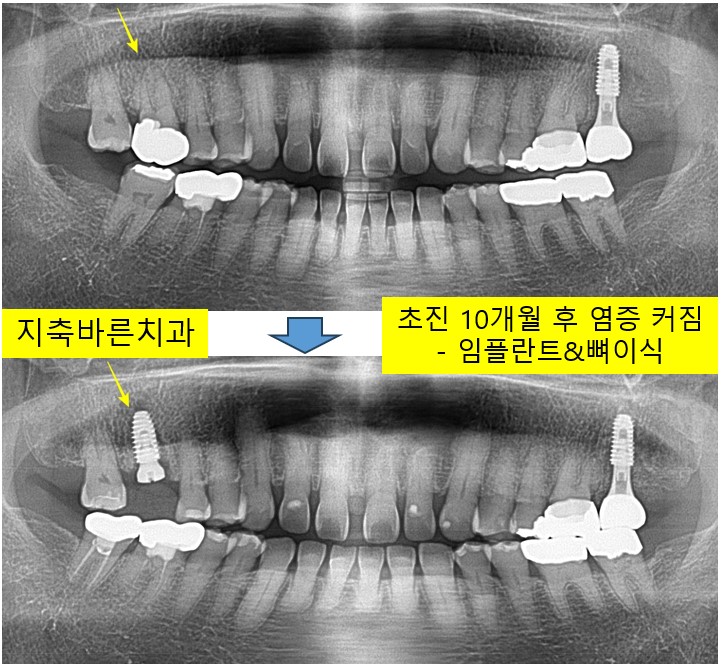

<치아에 염증, 아프지 않은데 치료해야하나요 - 염증 커짐>지축치과 지축역치과 삼송치과 원흥치과 원당치과 화정치과 종로치과 구파발치과 도래울치과 신원동치과 마두치과 서울역치과 미백

치아가 좀 흔들리는거 같고, 잇몸이 내려가 보이며, 충치검진을 위해서 2023년 11월 50대 Jㅁㅁ 님께서 내...